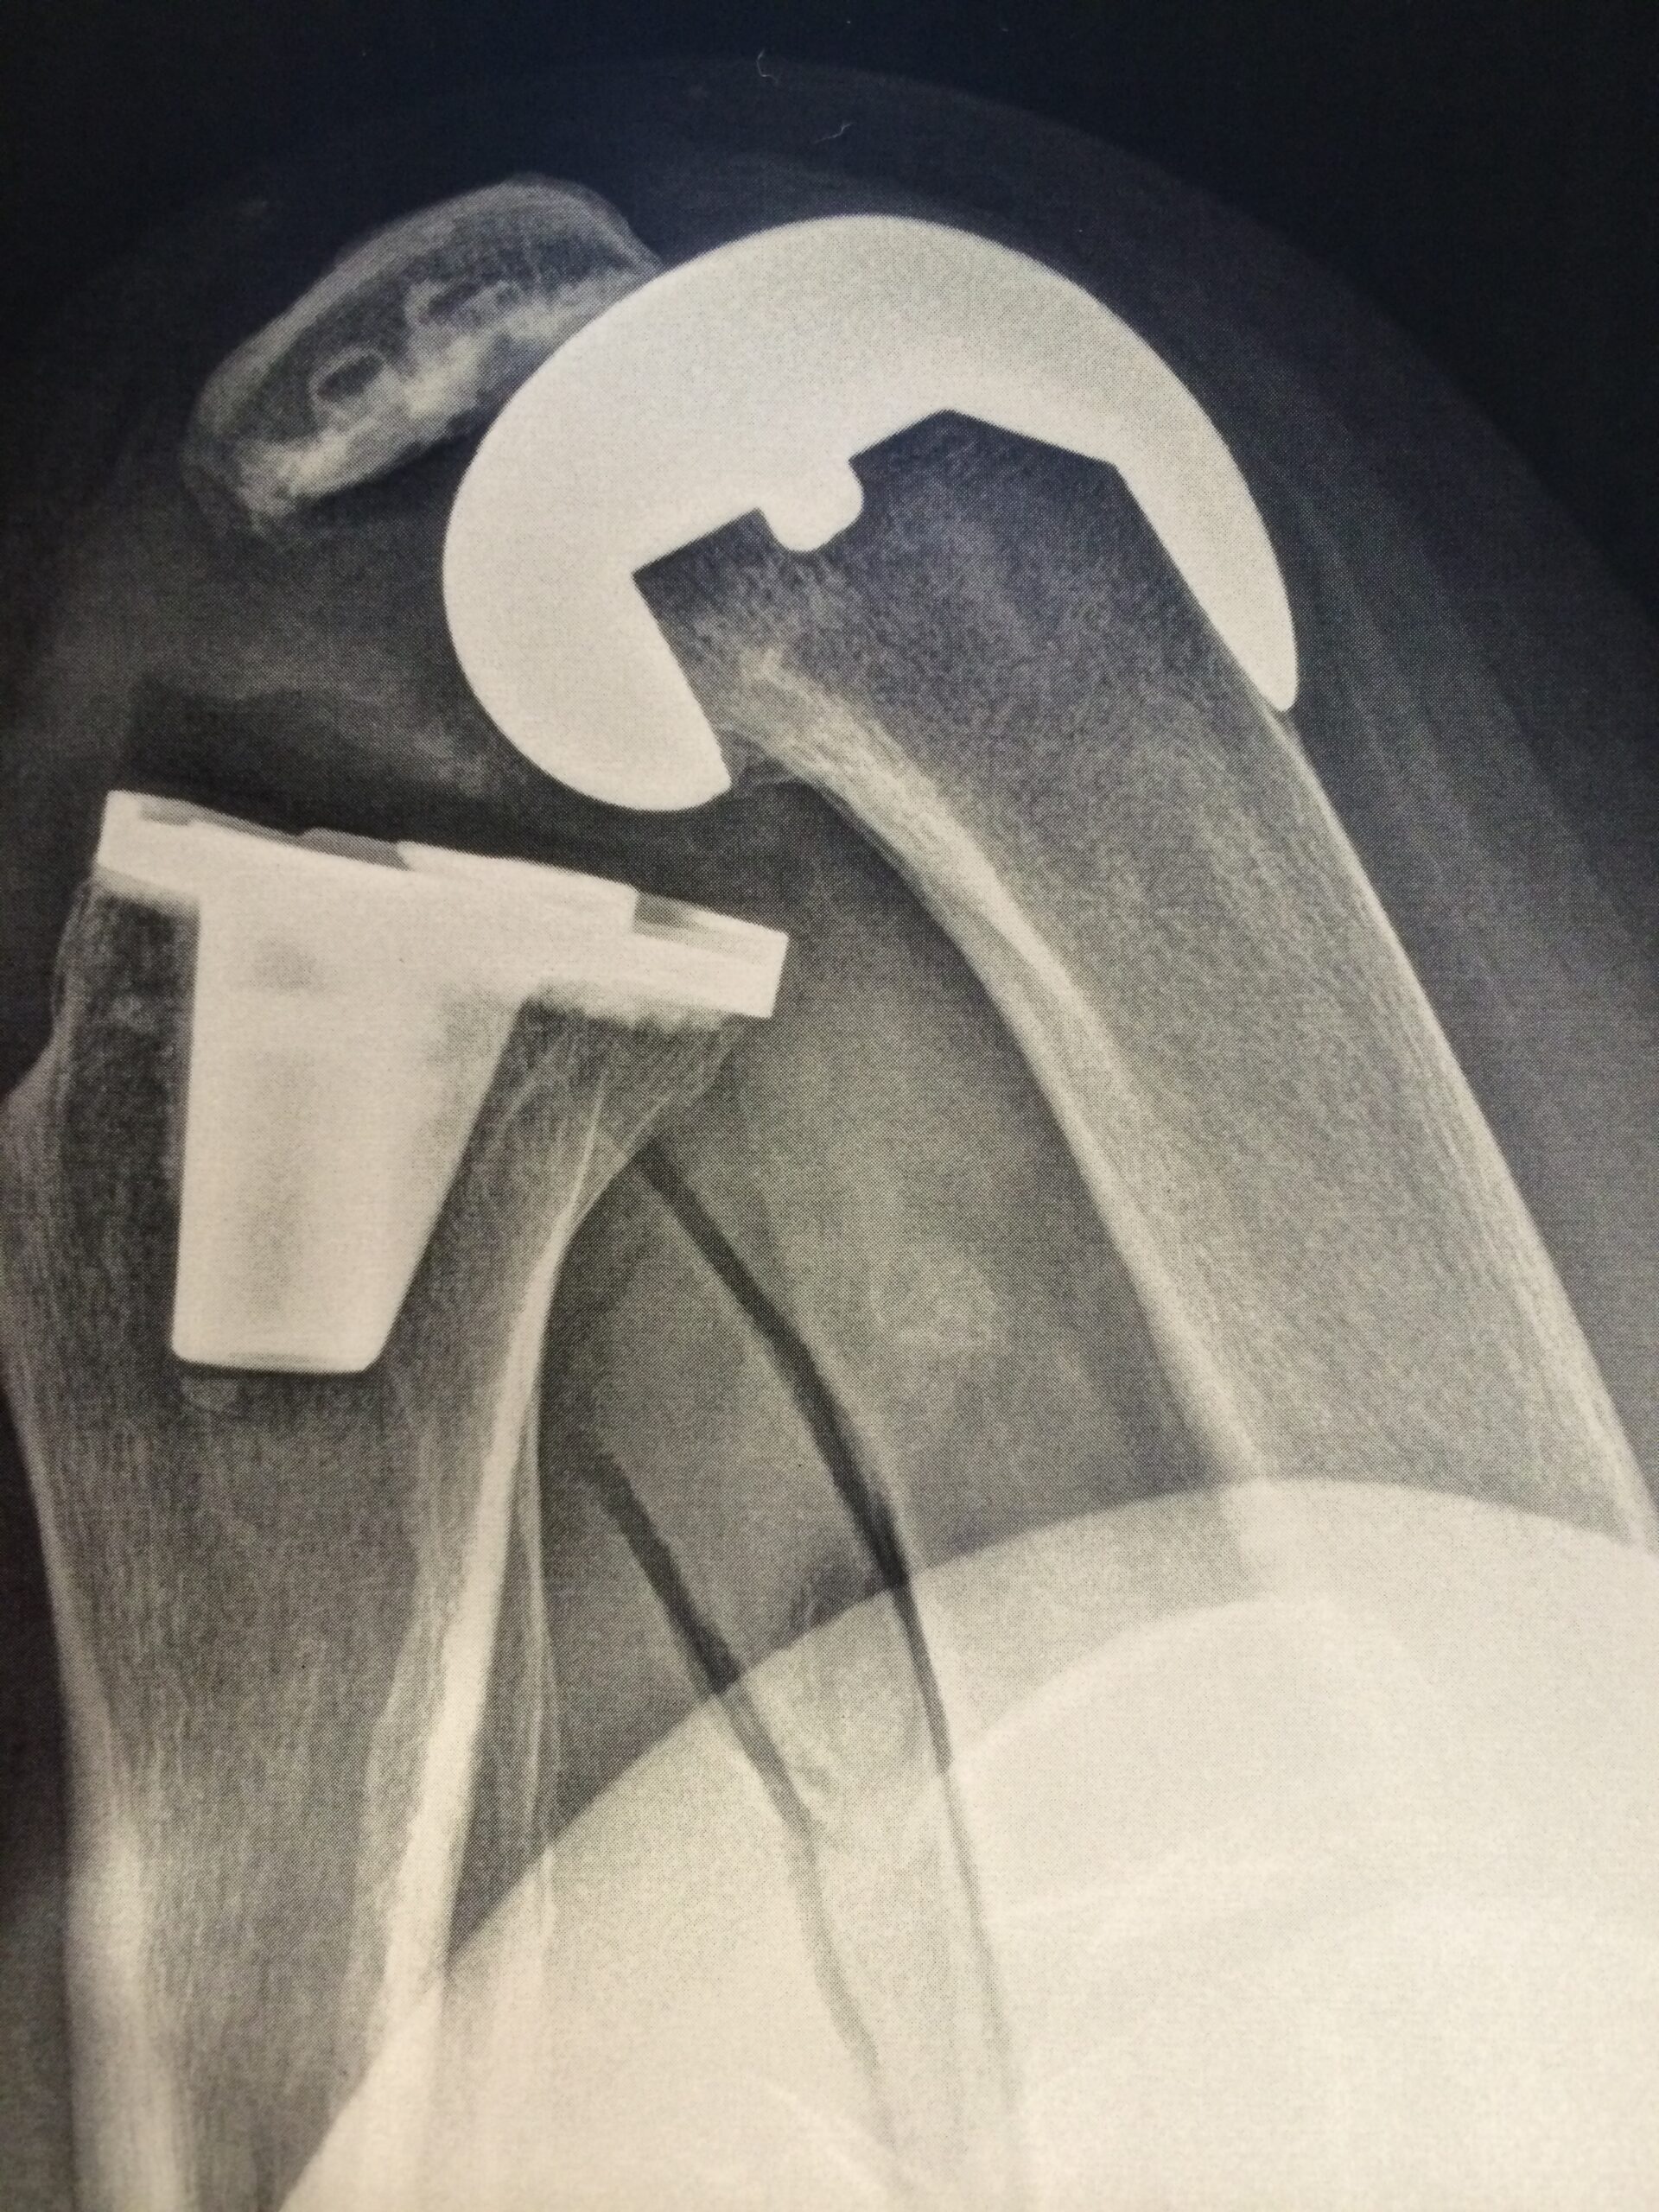

L’arthroscopie est une technique chirurgicale innovante, utilisée pour diagnostiquer et traiter les problèmes articulaires de manière précise et moins invasive. Spécialiste de cette approche, Dr. Synave propose des interventions par arthroscopie pour soigner diverses pathologies du genou, de la cheville, de l’épaule, et d’autres articulations.

Le docteur Synave pratique la chirurgie arthroscopique permettant de traiter sans ouvrir l’articulation grâce à une caméra et des instruments miniaturisés.